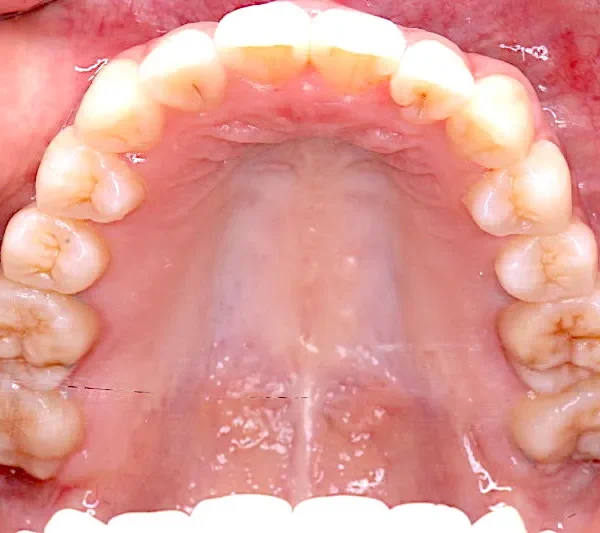

上下ガタガタで、下の歯は癒合歯(2本がくっついて1本の歯)です。

治療前と治療後で下の歯の銀歯がなくなっています。

コルチコトミーという矯正法で歯根への負担を軽減しながら治療しました。

治療回数71回、3年5ヶ月の治療期間で矯正治療を終了しました。

主訴が改善され、ご満足頂きました。